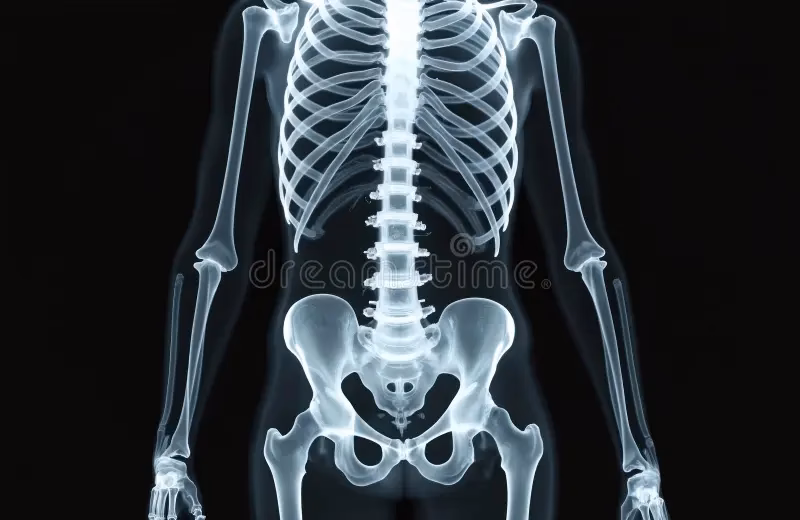

Hvad er en Radiografisk Knogleundersøgelse?

En radiografisk knogleundersøgelse er en diagnostisk billeddannelse, der bruger røntgenstråler til at tage detaljerede billeder af skeletsystemet. I modsætning til et enkelt røntgenbillede, der fokuserer på et specifikt område, undersøger en knogleundersøgelse typisk flere regioner eller endda hele skelettet. Dette gør den særligt nyttig til at identificere udbredte eller systemiske knogleproblemer.

Under proceduren tages en serie røntgenbilleder fra forskellige vinkler for at give et omfattende billede af knoglerne. Testen er ikke-invasiv og generelt smertefri, selvom du måske skal holde bestemte positioner kortvarigt, mens billederne tages. Processen tager typisk mellem 30 og 60 minutter, afhængigt af antallet af billeder, der kræves.

Testen udføres i en radiologisk afdeling eller et billeddiagnostisk center. Afhængigt af det område, der skal undersøges, kan du blive bedt om at ligge ned eller stå under proceduren. En radiograf vil betjene røntgenmaskinen for at tage billeder af dine knogler fra forskellige vinkler. For en helskeletundersøgelse tages der typisk billeder af kraniet, rygsøjlen, bækkenet, ribbenene, arme og ben, hvilket giver et omfattende overblik over dit skeletsystem.